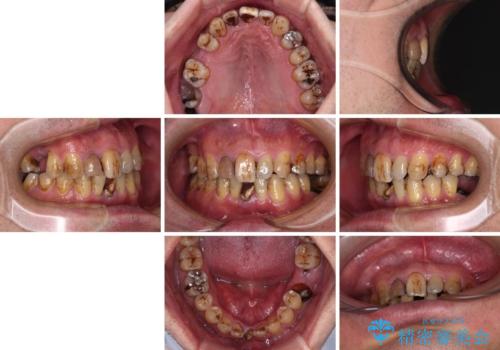

- むし歯治療途中で放置された歯が多く、スペースができたり歯が寄って来たりしているのを気にして来院された患者様です。

矯正治療を行いながら、欠損部はインプラントによる補綴治療を希望されたため、補助装置を用いたワイヤー矯正によりスペースを確保しながら歯列を整え、適宜インプラントを埋入していくこととしました。

上顎前歯もインプラントを希望していらっしゃいましたが、両隣の歯根が近接しており、インプラントは困難と判断したためオールセラミックブリッジによる補綴治療を前提として治療を開始することとしました。

在宅勤務のため、前歯にスペースが長期間できることに対して特に問題はないとおっしゃったため、スペースはそのままに治療を進めていくこととしました。